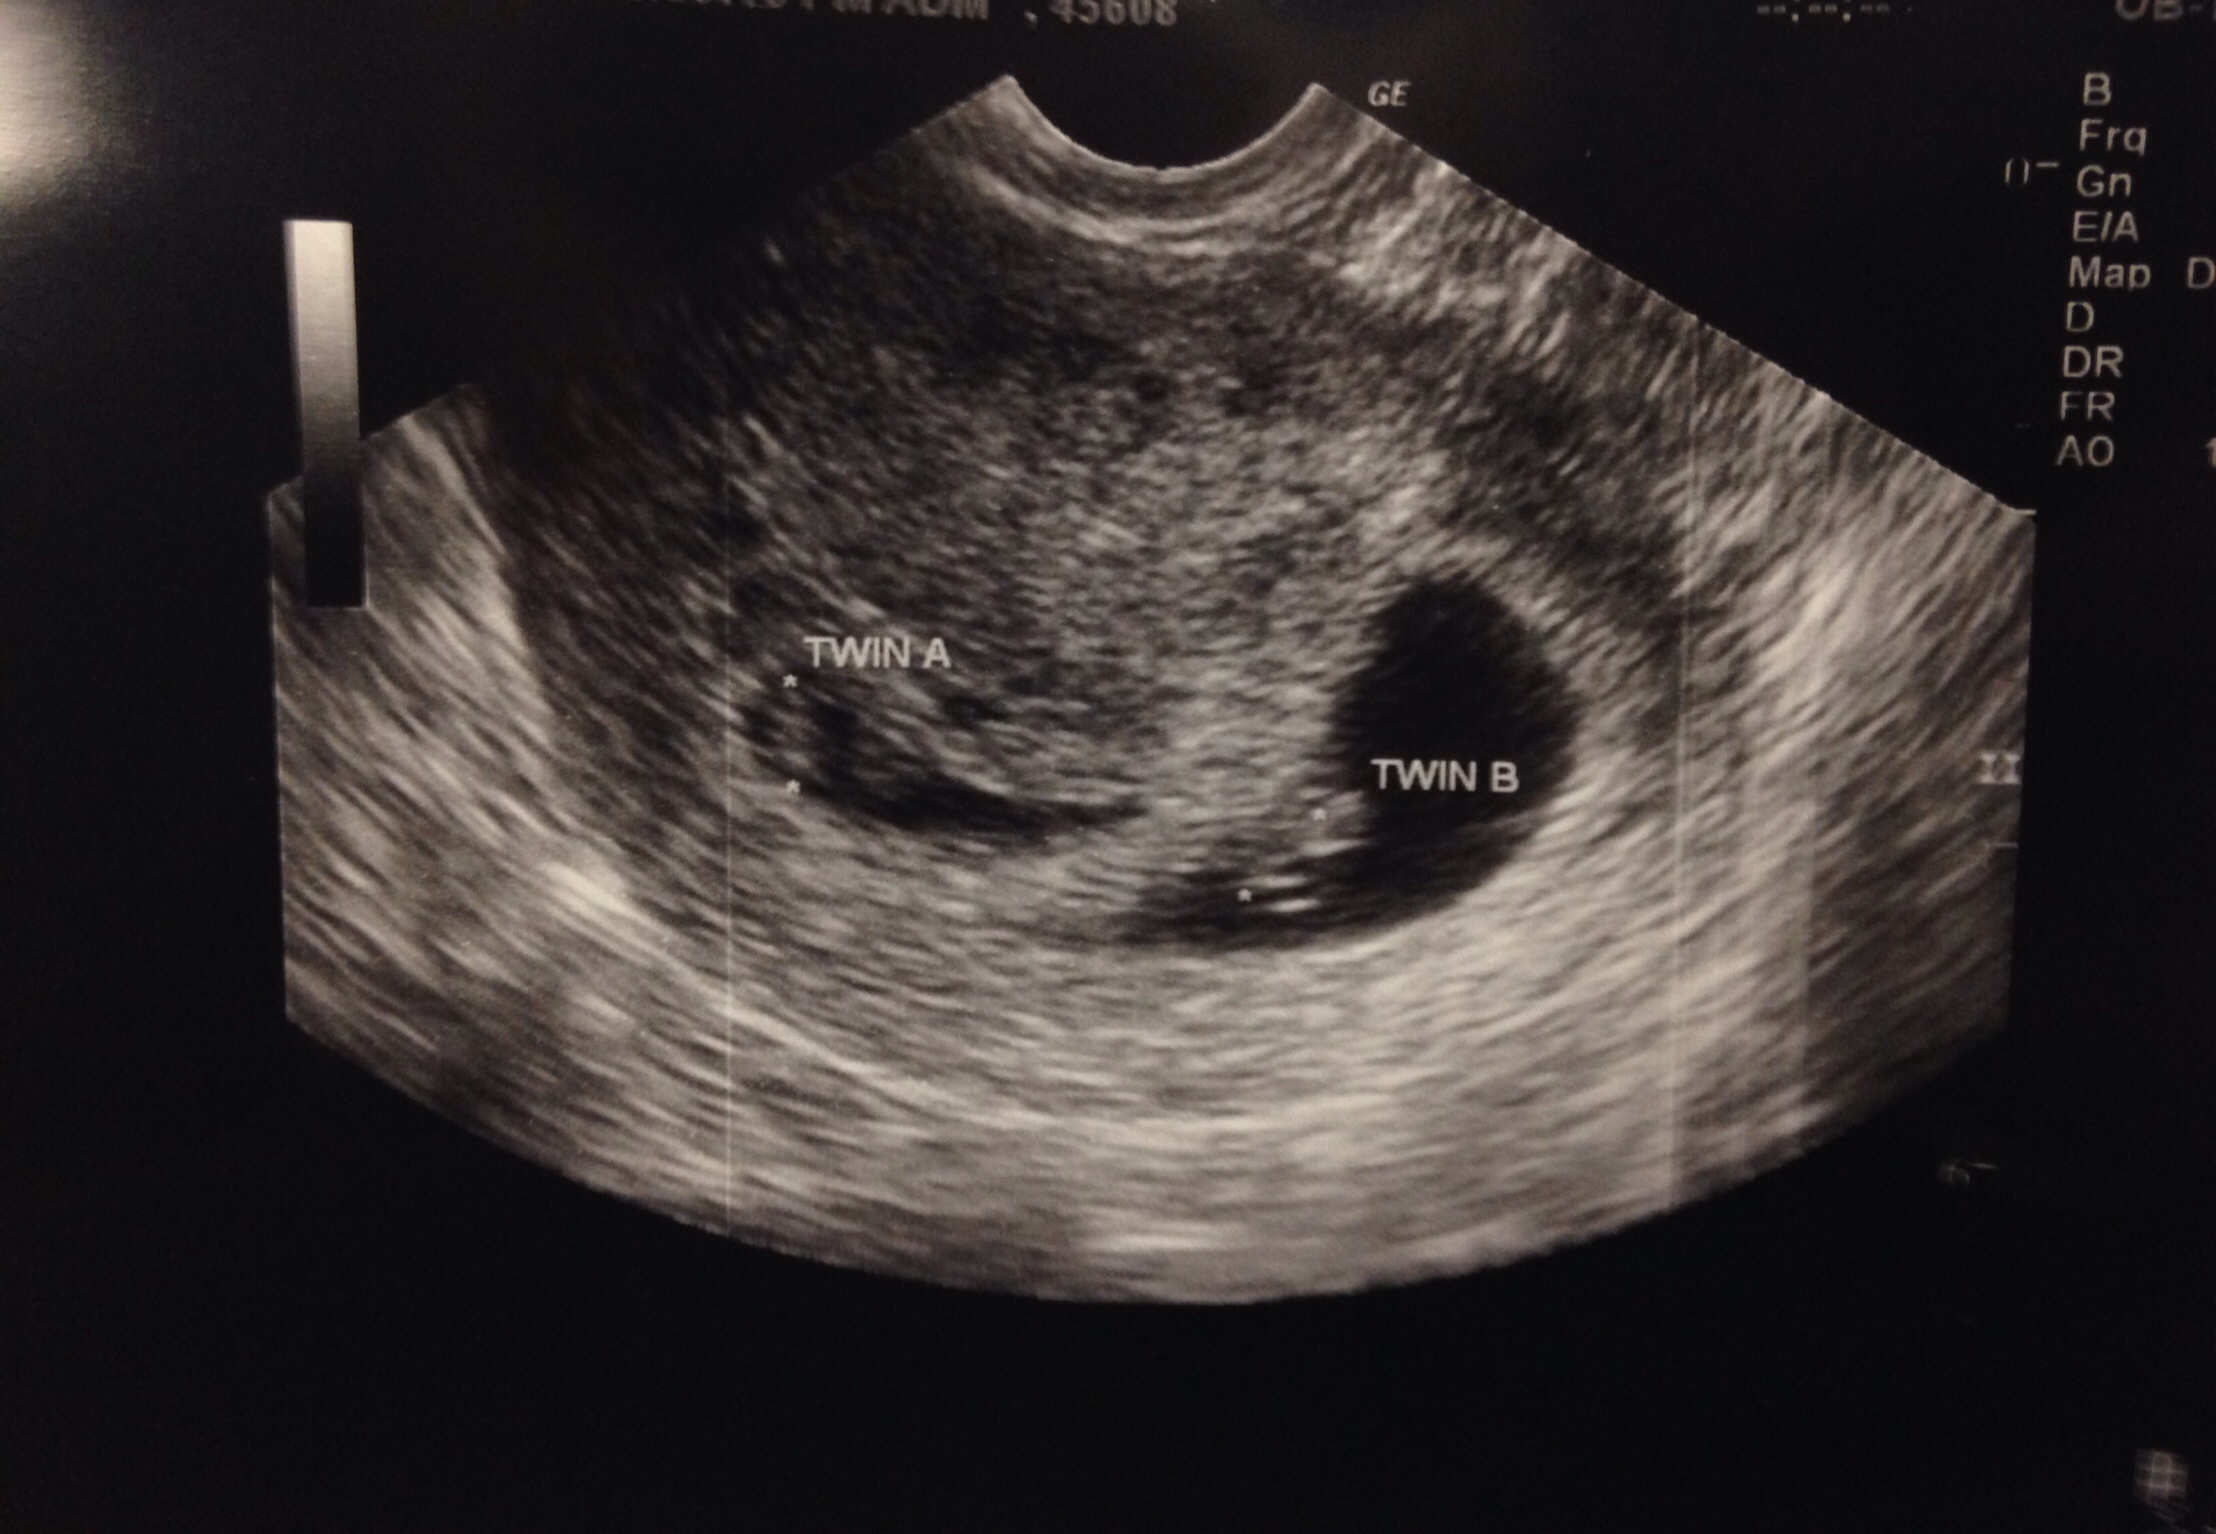

Hey all! My babies are a result of clomid. Is it more likely they are fraternal? Looks like two sacs and there were definitely two placenta. But the doctor only saw one corpus luteum. Could it be too early? Posted in my March thread also but figured you ladies may have some more insight :)!

• I'm 7 weeks 2 days. Could one of the corpus luteum have absorbed? Do we agree it's two sacs? Definitely two placenta but doctor was weary to say "two sacs" since he said it was early and lining could thin. But goodness they sure do look like two separate sacs

• If there are two placentas, there are definitely two sacs.

Your pictures look like di/di twins to me, but I'm no doctor.